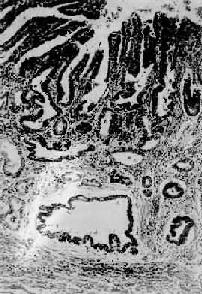

图10-18 胃硬

粘膜下层显著增生的纤维组织内有细胞浸润,细胞排成窄条索状